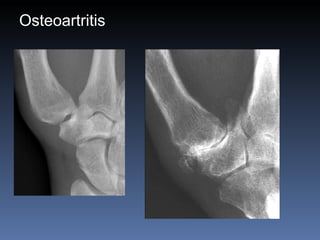

Osteoartritis IFDs, IFPs, 1 st  CMC Osteofitos Estrechez asimetrica del espacio articular  Esclerosis subcondral Quistes subcondrales No erosiones marginales Densidad osea preservada

Osteoartritis